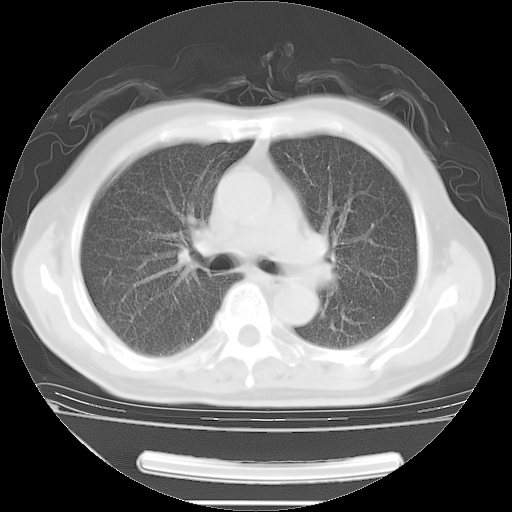

胸腹部CT,诊断意见:左上肺叶钙化灶、左侧胸膜局限性增厚并钙化、胆囊炎。描述部分肺组织呈磨玻璃样改变。